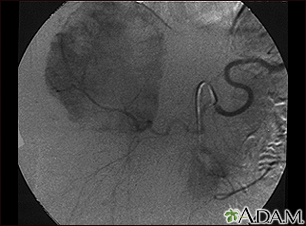

Hemangioma - angiogram